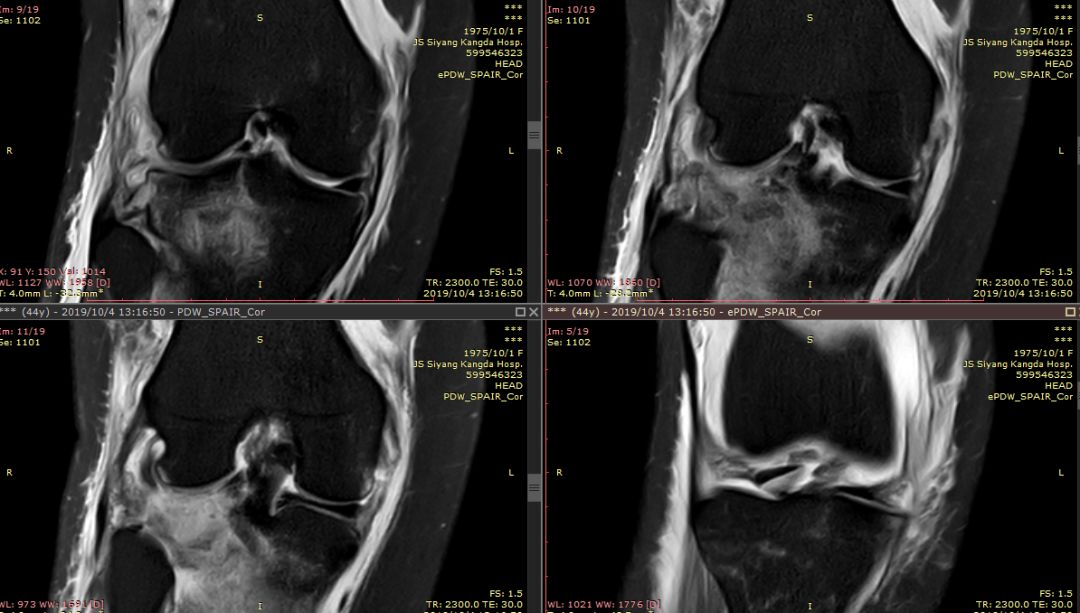

下图横断面的标线标记的是左下图,为外侧半月板的桶柄样撕裂移位

下图标记的是外侧半月板的撕裂

下图示外侧副韧带损伤 腘肌腱损伤 髂胫束连续

内侧副韧带损伤

膝后肌群损伤

Segond骨折,因下肢过度内翻、内翻暴力所致胫骨平台外侧缘的撕脱性骨折。撕脱的骨折块较小,小骨片多位于腓骨头上方,且较少波及关节面而易被忽视。往往合并前交叉韧带损伤、半月板损伤及外侧副韧带损伤。